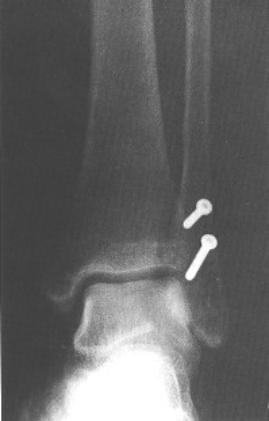

Fracturas del maléolo externo. Tratamiento con tornillos de compresión interfragmentaria.

Objetivo: Comparar la fijación interna de fracturas de peroné con tornillos de compresión interfragmentaria con el empleo de placa tercio de caña lateral

Métodos :Se estudiaron 43 pacientes divididos aleatoriamente en dos grupos, 22 tratados con tornillos de compresión interfragmentaria y 21 tratados con placa de tercio de caña lateral. Se evaluó tiempo quirúrgico, tamaño de la herida, tiempo de consolidación, dolor postoperatorio en el maléolo externo y resultado funcional medido al sexto mes de postoperatorio.

Conclusión: El empleo de osteosíntesis mínima en el tratamiento de fracturas de peroné es un método seguro y efectivo en pacientes adecuadamente seleccionados.

Figura 1